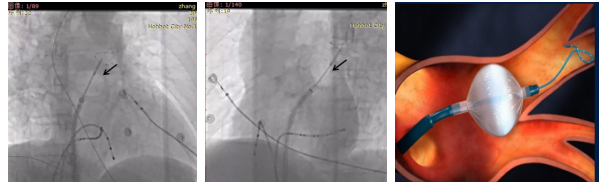

术中冷冻消融影像与冷冻球囊封堵模式图

(黑色箭头处为冷冻球囊):